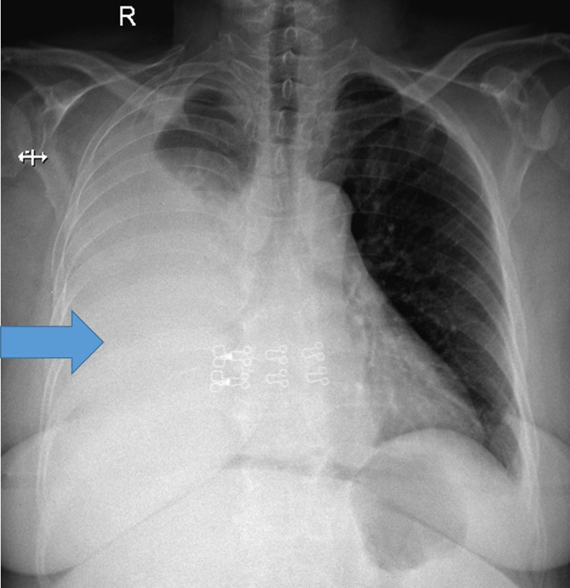

This complication (depicted here) of cirrhosis can occur in excess of 500ml of ascitic fluid and typically accumulates around the posterior lobe in CTs due to porous or ‘bare’ nature of the right posterior diaphragm.

Hepatic Hydrothorax

Typically occurs on the right posterior lobe/right hemidiaphragm as the left is thicker and more muscular. 73-85% on the right.